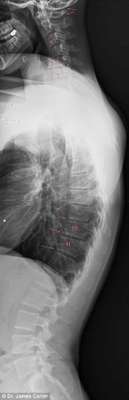

As imagens de raio-x abaixo mostram os malefícios do uso excessivo de smartphones e tablets para o corpo de adolescentes e crianças. Espinhas dorsais completamente curvadas que resultam em problemas graves de coluna e para o pescoço é a principal consequência da tecnologia para a saúde da nova geração.

17 anos, 16 anos e 7 anos

17 anos, 16 anos e 7 anos - Dr. James Carter

A condição, chamada de ‘text neck’ (‘Pescoço de mensagem’, em português), é observada em pessoas que sentam com suas cabeças a frente do corpo para interagirem com os seus smartphones ou tablets durante algumas horas.

Em geral, o peso da cabeça humana varia entre 4,5 kg e 55, kg, e a projeção do pescoço para frente faz com que o peso seja mais difícil de suportar, o que aumenta a probabilidade do surgimento de dores musculares e o encurvamento da espinha dorsal.